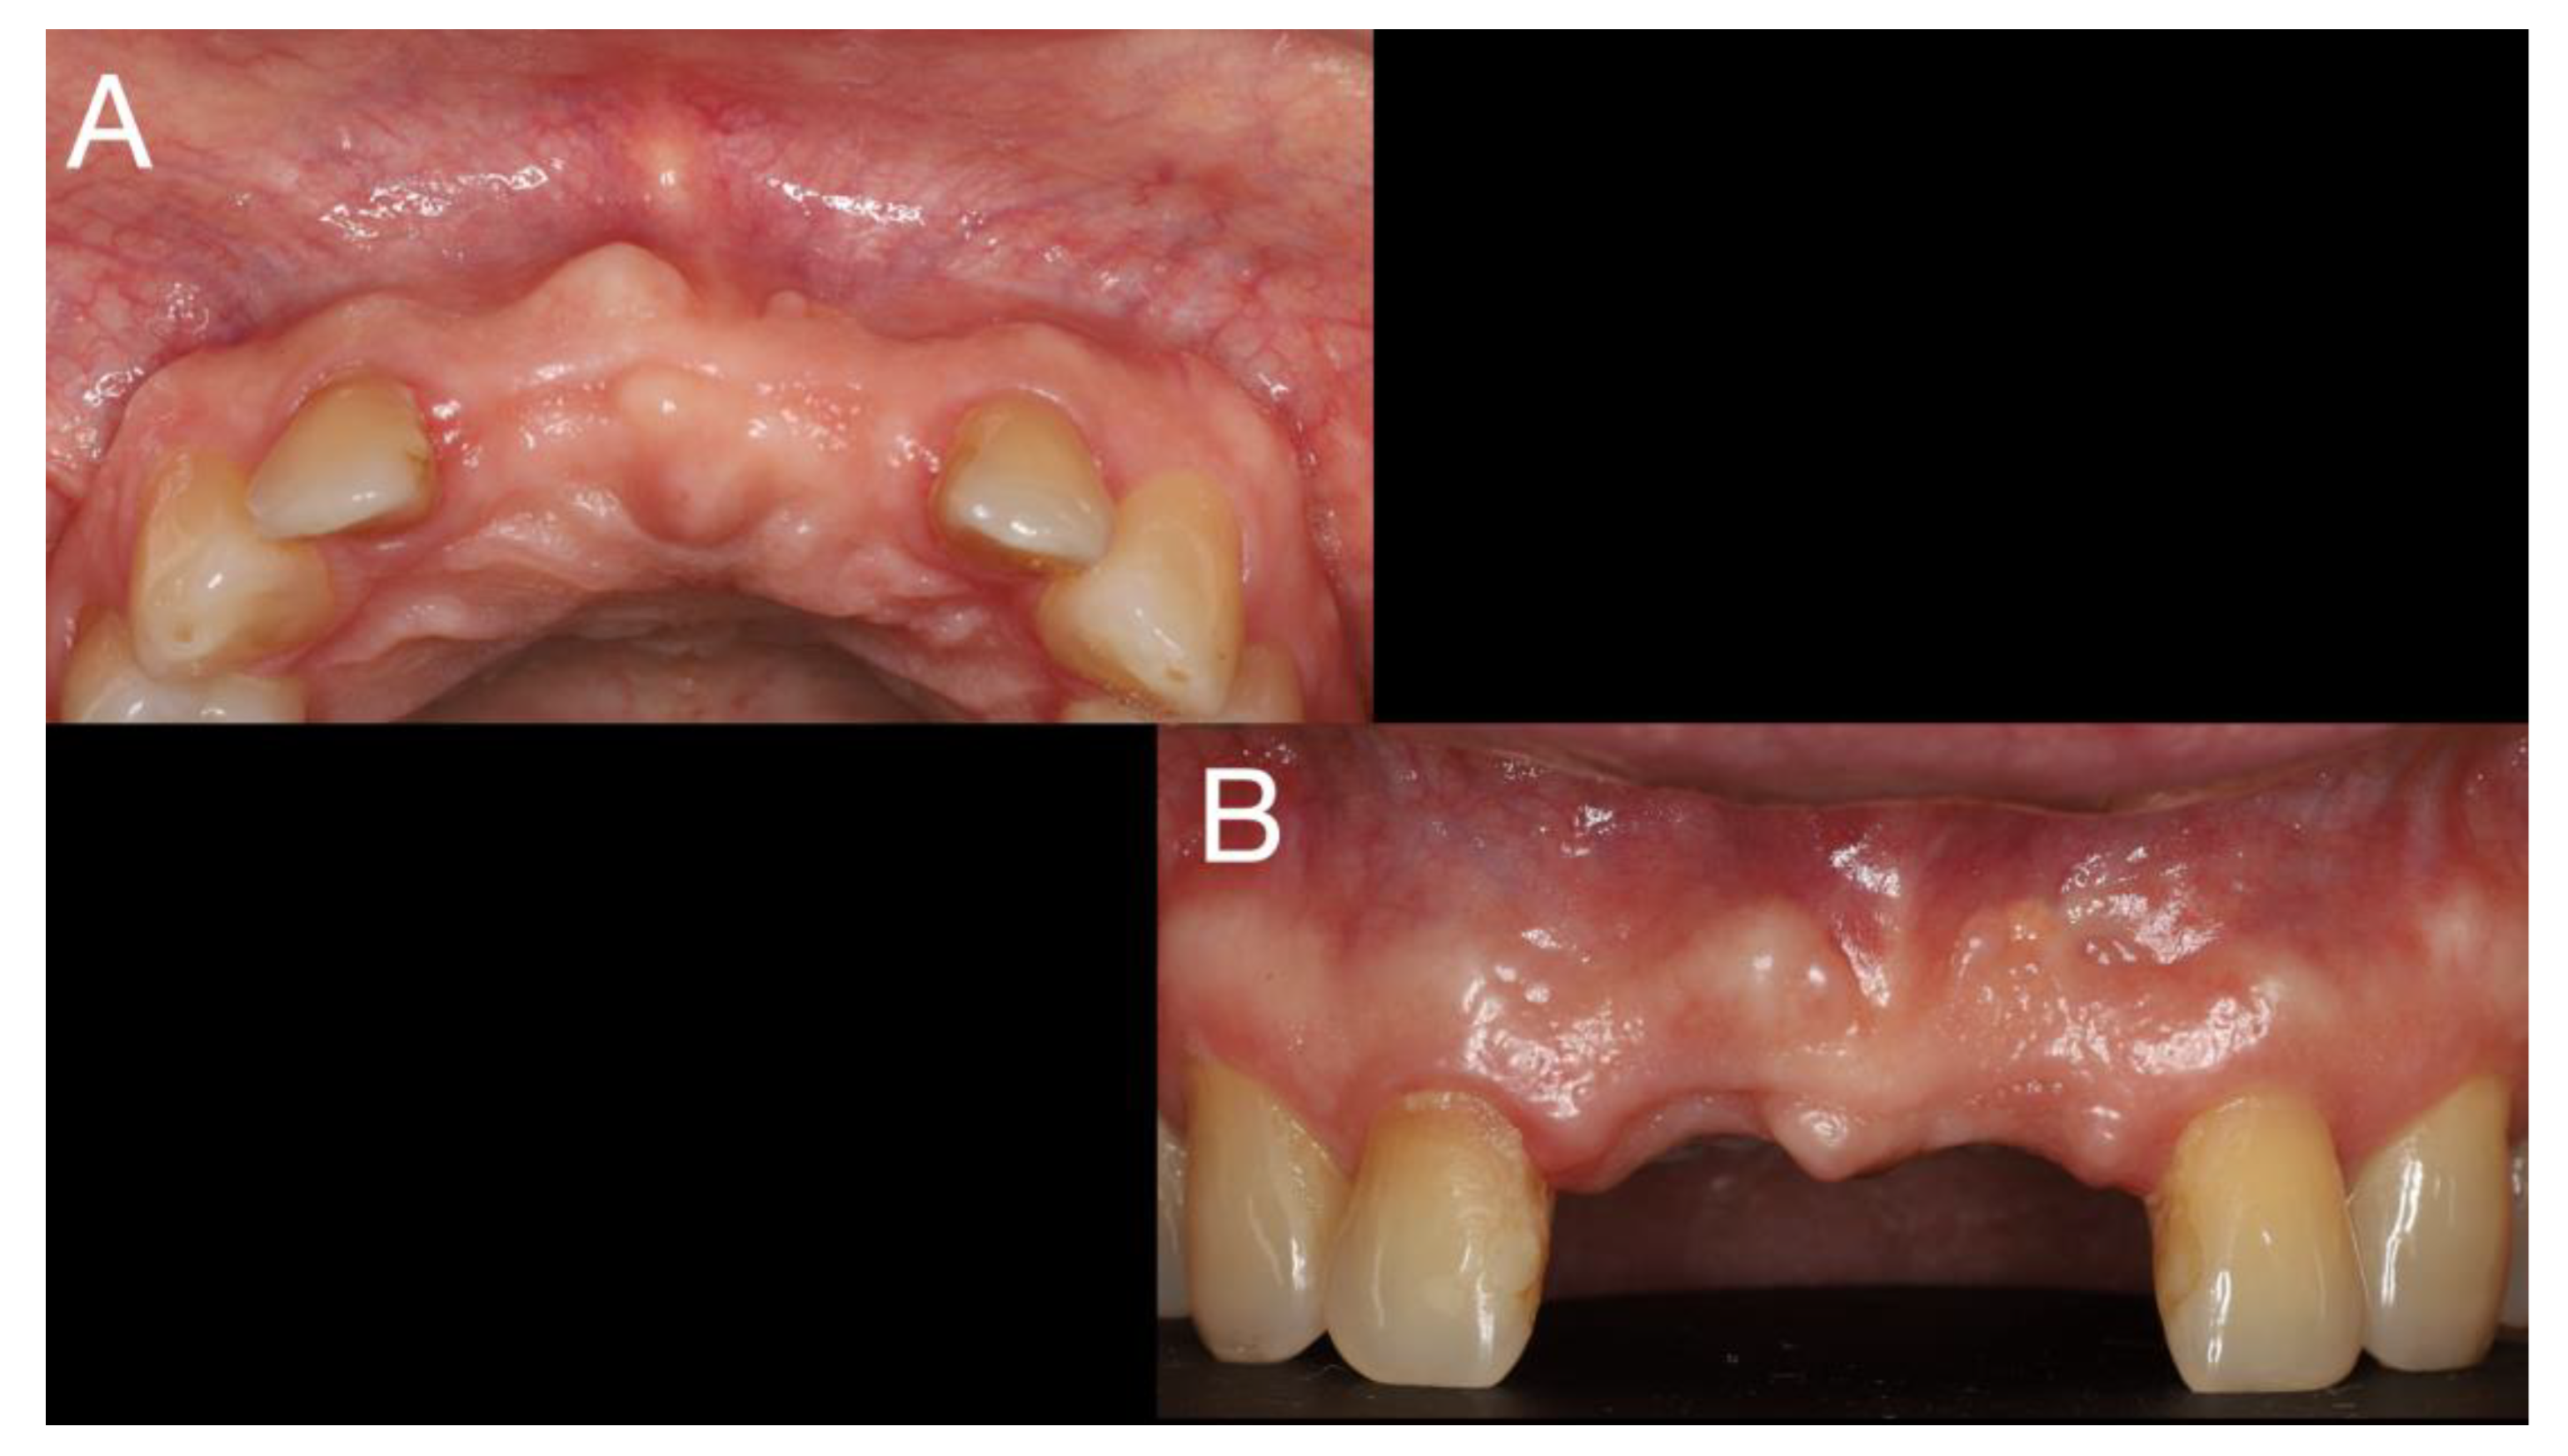

After 6 weeks for healing of soft tissue (Figure 3), the surgery of cyst enucleation and guide bone regeneration with fence technique [9] was performed.

Figure 3. 6 weeks after tooth extraction with healead of soft tissue – A -frontal view; B - occlusal view.

Preprints 77316 g003